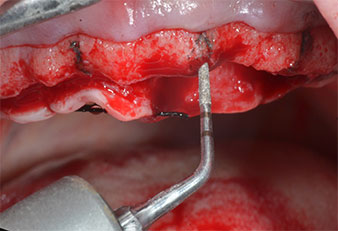

A flame-shaped, diamond-coated piezoelectric instrument (Piezomed I1) was used to mark the implant positions and to perform pilot preparation (Fig. 3). Care was taken to use an up and down movement, with reduced power, full irrigation and low pressure (below 300 g). Next a pilot instrument (Piezomed I2A/I2P) was applied for the initial 2 mm diameter enlargement of the implant sites (Fig. 4), followed by a 3 mm insert (Fig. 5).

In the present case the Z25P and Z35P instruments were not used due to the relatively soft posterior bone, which was easily managed with the I3A/I3P.